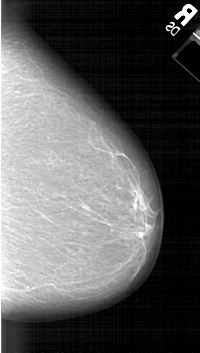

A_1308_1.LEFT_CC

LEFT_CC LINES 6286 PIXELS_PER_LINE 3556 BITS_PER_PIXEL 12 RESOLUTION 43.5 OVERLAY

FILE: A_1308_1.LEFT_CC.OVERLAY

TOTAL_ABNORMALITIES 1

ABNORMALITY 1

LESION_TYPE MASS SHAPE LOBULATED MARGINS ILL_DEFINED

ASSESSMENT 4

SUBTLETY 3

PATHOLOGY BENIGN

TOTAL_OUTLINES 1

BOUNDARY